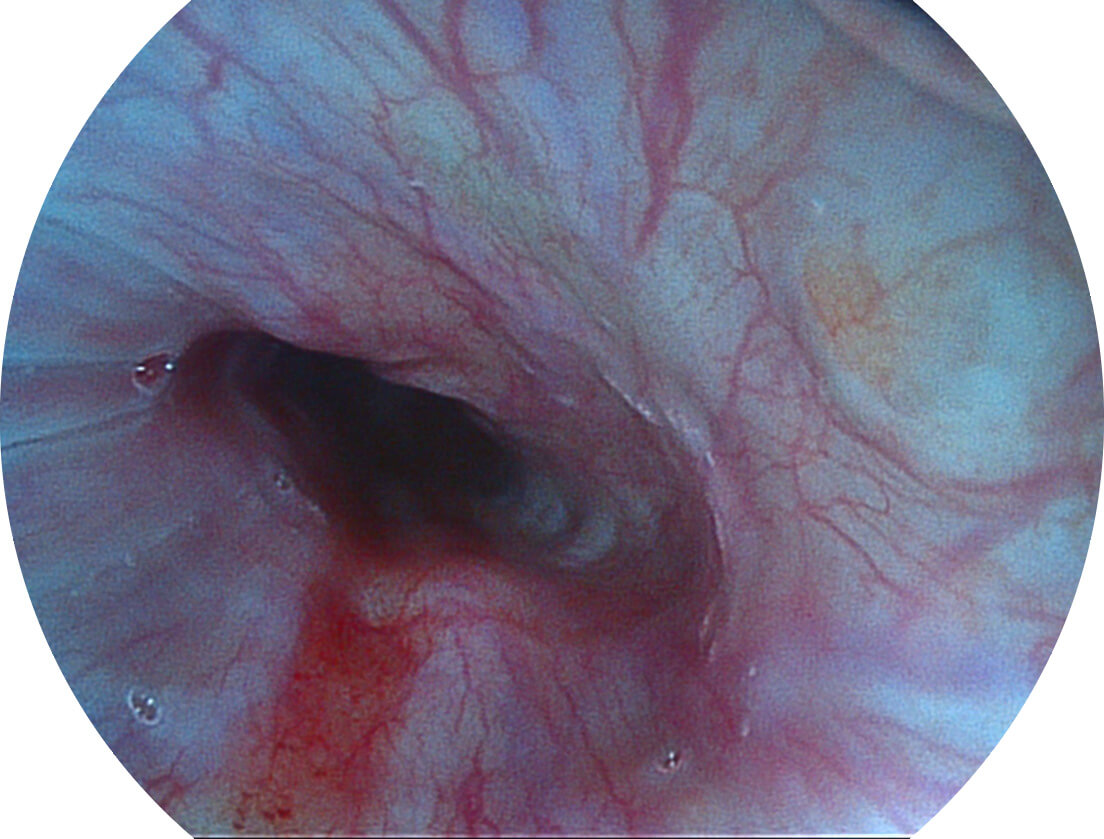

图像具有高亮度、高黏膜血管颜色对比度的特点,且不改变粘液、食物残渣、粪便的基本颜色,可在中远景下进行观察,助力消化道早期疾病的诊断。

SFI图像